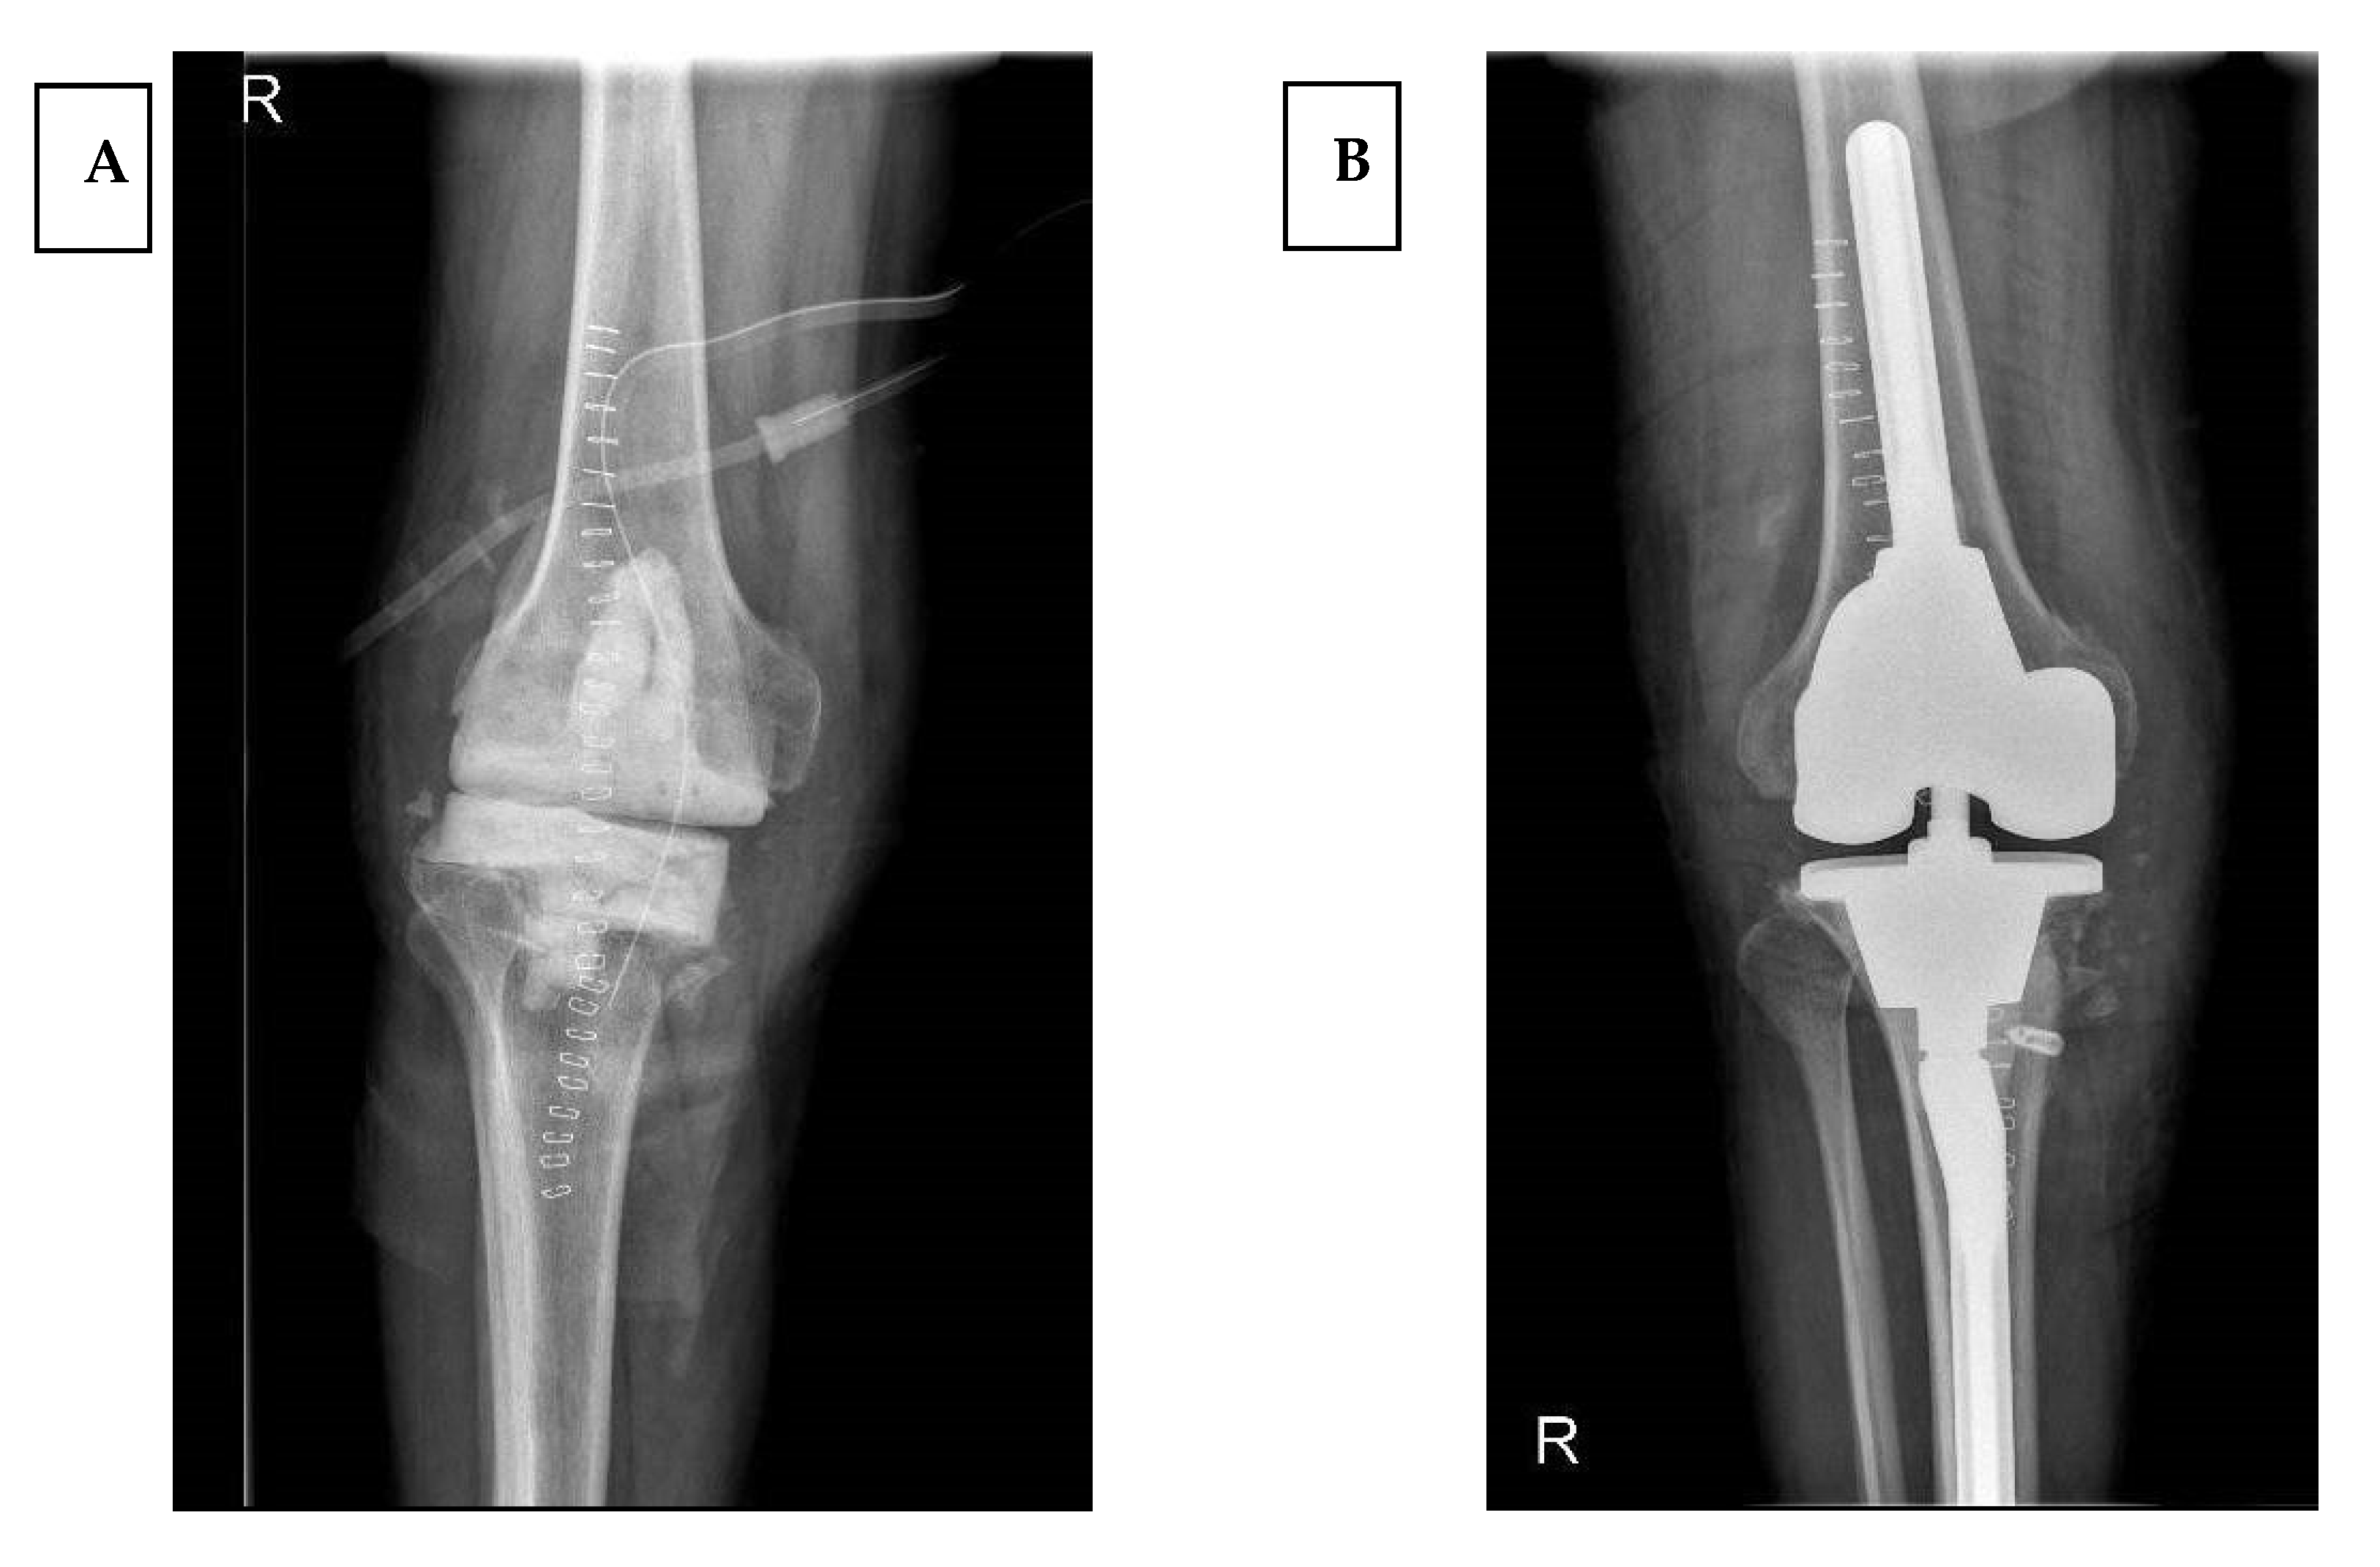

Revision Total Knee Arthroplasty Using a Constrained Condylar Knee Prosthesis in Conjunction Constrained Hinged Knee Replacement Tibiofemoral instability is increasingly recognized as a common mode of failure in total knee arthroplasty. There is debate in the literature whether rotating hinge knee (rhk) or. Gunston introduces first cemented surface arthroplasty of knee joint 1970 guepar develops a new hinged prosthesis based on design by walldius that increases motion. To address instability in primary tka, implants with varying. Constrained Hinged Knee Replacement.

Revision Total Knee Arthroplasty Using a Constrained Condylar Knee Prosthesis in Conjunction Constrained Hinged Knee Replacement Gunston introduces first cemented surface arthroplasty of knee joint 1970 guepar develops a new hinged prosthesis based on design by walldius that increases motion. Rotating hinge knee prostheses (with or without distal femoral replacement) are indicated in cases of unreconstructible bony or soft tissue compromise. Hinged implants are the most constrained knee replacement prostheses. Despite this, there are few published. Constrained Hinged Knee Replacement.